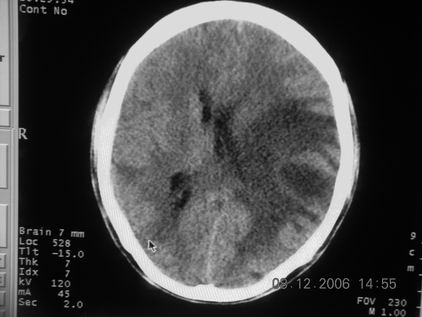

标题: CT11164:男,46岁,白血病患者,,大家看看. [打印本页]

标题: CT11164:男,46岁,白血病患者,,大家看看.

以前的片子,病史忘了,男,46岁,白血病患者,后来到中山二院诊断为

谁见过白血病中枢系统改变是怎么样的吗?

白血病脑浸润。

支持白血病脑浸润.

1 多发脑脓肿可能性大.>2 白血病浸润.

白血病脑浸润。没见过!但结合病史应首先考虑此病。

支持白血病脑浸润

结合病史考虑白血病脑浸润。

结合白血病病史,支持考虑白血病脑浸润。

结合病史考虑白血病脑浸润